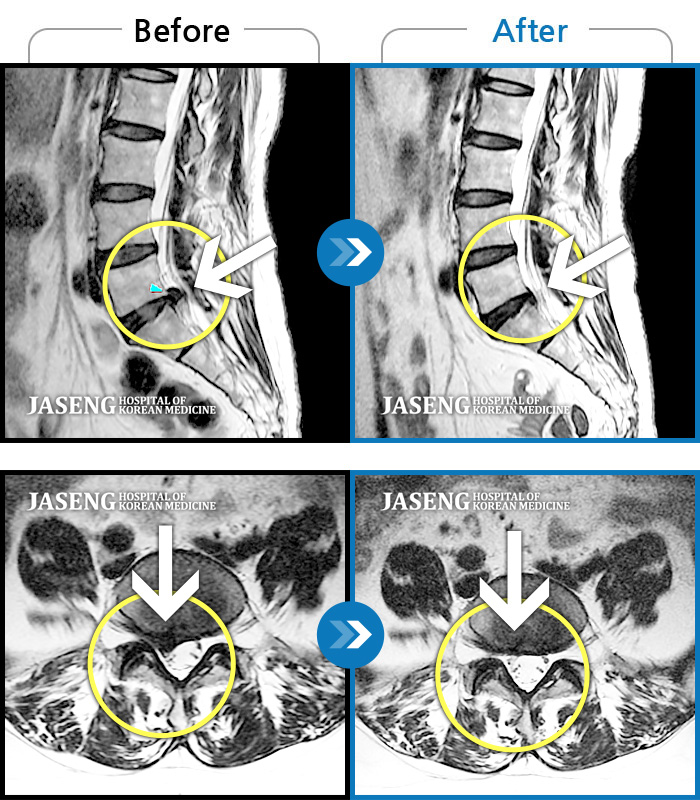

허리디스크

보라매 · 빈상은 원장

좌측 허리부터 고관절 통증이 심하고 다리까지 저려서 허리를 똑바로 펴기 힘들어요.

촬영시기

2020.07.27 ~ 2023.01.20

2023.11.24

조회수 515